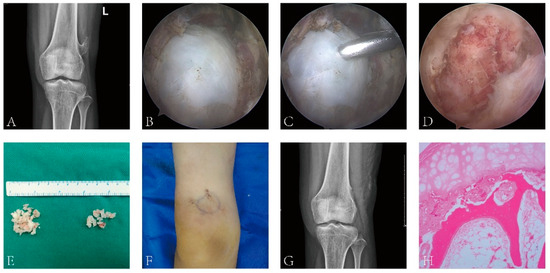

Figure 1.

Image data of arthroscopic resection of extra-articular osteochondroma of the knee. (A) Preoperative X-ray can clearly show osteochondroma, and the tumor and surrounding tissue are clearly demarcated; (B) the tumor can be clearly observed by arthroscopy during the operation. (C) A small tumor was removed with rongeur. The tissue was sent to rapid pathological examination during the operation. (D) The tumor tissue was gradually removed with rongeur, and a few normal bones were removed. (E) The tumor tissue was completely removed to reduce the cell spreading. (F) Two small incisions. (G) Postoperative review of X-ray showed that the tumor had been completely removed. (H) Osteochondroma was confirmed after postoperative pathological examination.

Two arthroscopic incisions were made at the upper and lower side of the tumor mark, followed by local blunt dissection with vascular forceps or periosteal exfoliator, reaching the bone surface and creating a cavity. After the arthroscope was placed, the local soft tissue was cleaned with a shaver to expose the tumor tissue and its borders (Figure 1C), and part of the tumor tissue was removed with a nucleus pulposus forceps and sent for rapid pathological examination during the operation (Figure 1D). After the benign tumor was confirmed, arthroscopic resection was performed. First, the cartilage cap was burned off with a radiofrequency knife, and then, the tumor was completely removed from the root of the tumor with an osteotome. If the tumor was too large, it could be cut into small pieces with a nucleus pulposus forceps and then taken out (Figure 1E,F). In order to avoid tumor tissue’s dissemination and colonization into other parts or causing the surgical site to excessively swell, attention was paid to maintaining smooth drainage of the irrigation fluid during the operation. There was no need to place drainage after surgery, but an elastic bandage was used for local compression. As soon as the wound pain was relieved postoperatively, passive flexion and extension of the knee and weight-bearing activities were conducted, and the X-ray inspection was reviewed (Figure 1G). The final diagnosis depended on the postoperative pathological results (Figure 1H).